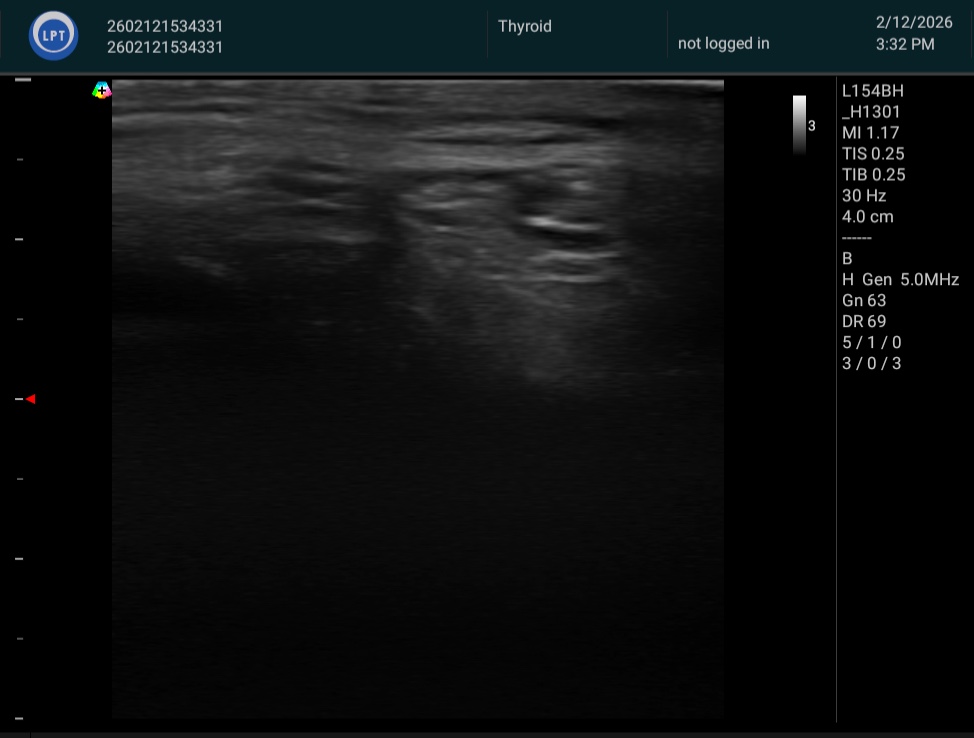

施術前後の変化をエコー画像・ノギス計測によって客観的に記録しています。

脂肪体が「膨らむ」——その事実を、数字と画像がそのまま示しています。

すべて、たった1回の施術後の計測です。

※ 個人差があります。掲載の計測値はすべて実際の施術前後の計測結果です。

※ エコー画像・ノギス計測は施術効果の参考として提示しています。